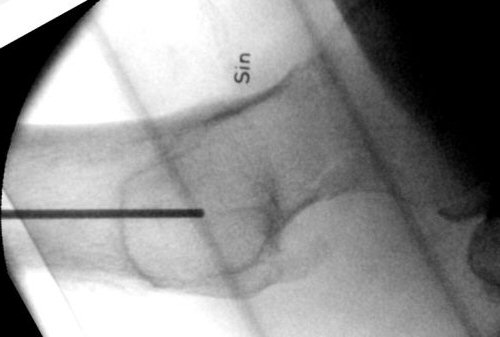

K-tråd hålls längs femur på sidobild. Markera längsgående linje ca 1 cm dorsalt om denna.

- Använd pryl för att göra hål i kortex vid tänkt ingång, inte längre distalt än trokanter minors distala kant på frontalbild och någon cm dorsalt om centrum i sidobild.

- Borra med k-tråd, tråden ska gå nära kollums distala kortex i frontalbild och centralt i kollum i sidobild. Änden på k-tråden ska sluta ca 5 mm från kaputs broskkant.